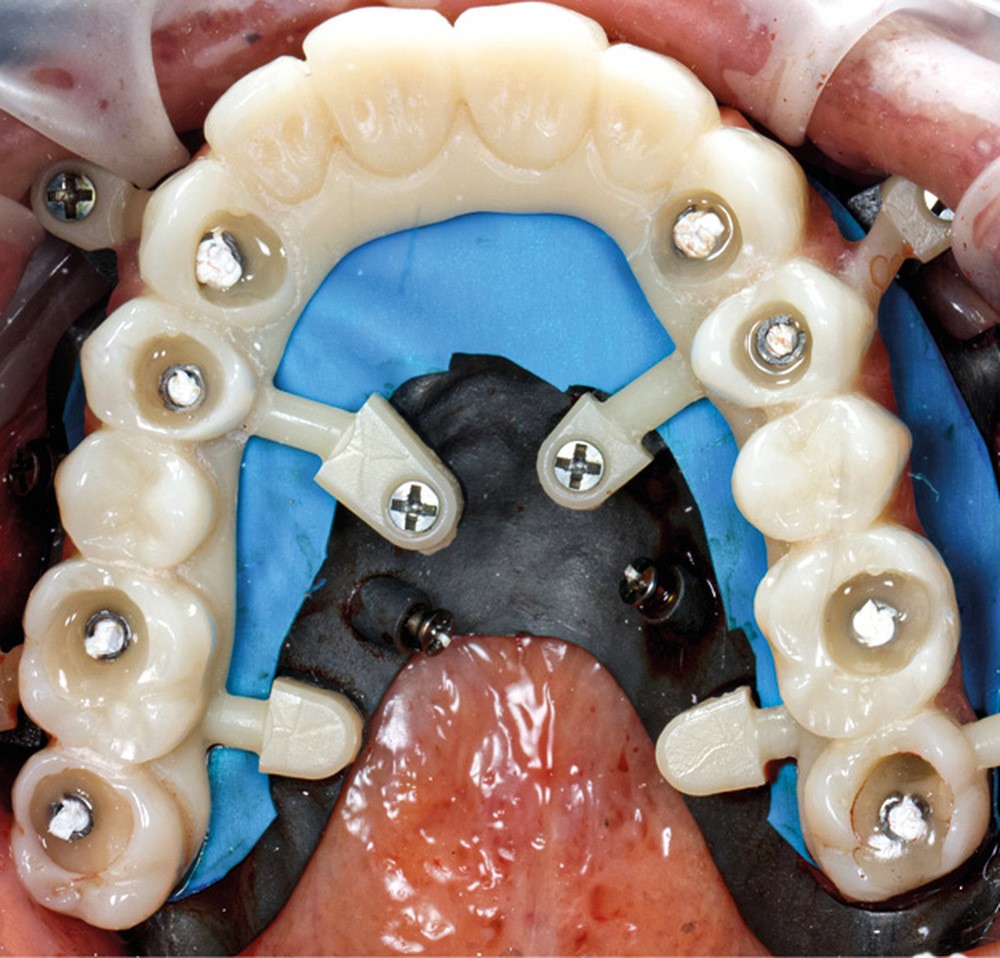

Après une extraction atraumatique des dents résiduelles, nous passons au 3e étage qui est le guide de forage stéréolithographique. La séquence de chirurgie Full guided est passée et les implants ont été torqués entre 40 et 50N.cm2 (fig. 6, 7, 8). Cette stabilité primaire dans les sites d’extraction et des sites greffés a permis la mise en charge immédiate du bridge complet provisoire. Des études cliniques [3, 4, 5] ont montré que la mise en charge immédiate dans les sinus greffés ne pose aucune contre-indication. Le 4e étage est donc celui du bridge provisoire transvissé à l’étage de base et solidarisé en bouche par l’intermédiaire de cylindres provisoires sur piliers MUA, avec une colle duale (GC-LinkForce). L’espace entre les implants et l’alvéole a été comblé par une xénogreffe (Bio-Oss Geistlich). Les profils d’émergence sont travaillés et parfaitement polis. Enfin, le bridge est mis en place, torqué à 20.cm2, équilibré et les consignes postopératoires ont été rappelées à la patiente (fig. 9 et 10).